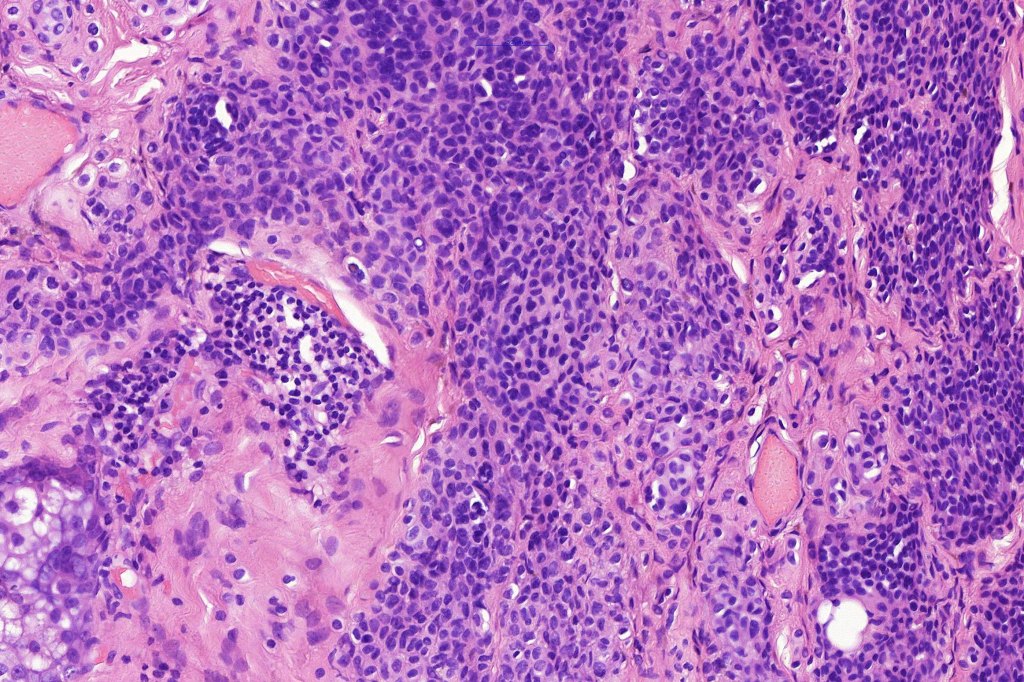

Histological features

.Balloon cell change is most often seen in banal melanocytic nevi but it has also rarely been described in cellular blue nevus, dysplastic nevus, combined nevus, halo nevus & Spitz nevus. Lesions with <50% of balloon cells are sometimes described as nevi with balloon cells. Nevi with >50% balloon cells are described as balloon cell nevus.

.Balloon cell nevs genrally has uniform, hyperchromatic nuceli (as opposed to the vesicular nuclei with prominent nucleoli) seen in melanoma. Mitoses are absent.(In my experience, balloon cell melanoma is more common than balloon cell nevus).

The importance of the entity is that it must always be distinguished from balloon cell melanoma. All cases should be scrutinized very carefully for pleomorphism and mitotic activiy before rendering a diagnosis of balloon cell nevus.